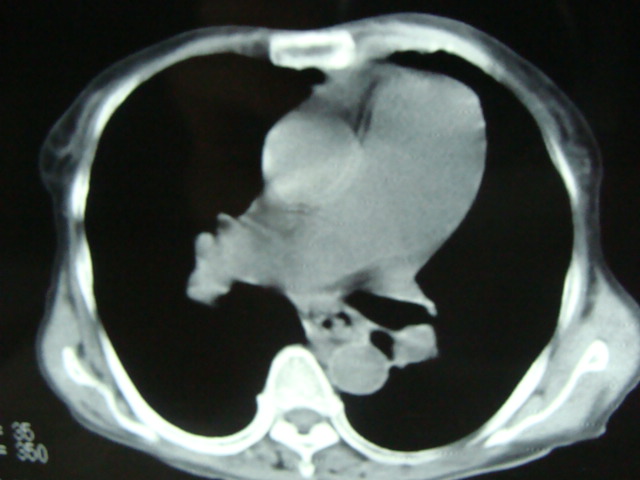

以下是引用老爱克斯新网客在2008-6-2 6:38:00的发言:[br]ct表现是肺动脉根部明显扩张,右心室增大,左房左室及右房都不大,因此可以除外风心。高血压心脏病。冠心病。定位片基本可以除外肺心病,(心肌病。心包积液更不可能)因此除外了后天性获得性心脏病。其表现也可以除外室缺。房缺。动脉导管未闭等常见的先心病。如果是原发性肺动脉高压除肺动脉根部扩张外双侧肺动脉尤其是右下肺动脉干应该也有扩张。因此我认为最大的可能是肺动脉瓣狭窄伴有窄后扩张,建议做一下彩超就知道了。期待结果。